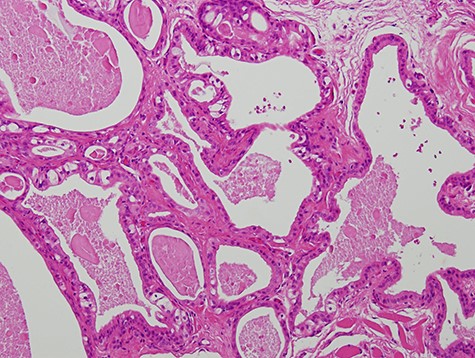

A 63-year-old man was referred to our hospital for treatment of a nodule on his tongue in May 2003. His medical history included Wolff–Parkinson–White syndrome and atrial fibrillation, both of which were controlled adequately by his primary care physician. Physical examination revealed very slight swelling at the right edge of his tongue. The patient reported some spontaneous pain. It was diagnosed as inflammation of the foliate papilla; the patient was followed-up with a gargle prescription. In September 2005, an elastic soft mass, 4 mm in diameter, was observed along the right edge of his tongue (Fig. 1). It was clinically diagnosed as a benign tumour and removed under local anaesthesia. Microscopically, the lesion was composed of multiple cysts of various sizes and shapes, with or without papillary intraluminal short projections (Fig. 2). Many cyst cavities contained eosinophilic fluid. The lesion was well-delineated, but the capsular structure was ill-defined. The stroma was fibrous connective tissue without lymphocytic components. The cystic cavities were lined by a bilayered epithelium composed of luminal columnar cells and basal cuboidal cells. Both luminal and basal epithelial cells were eosinophilic; some clear cells were seen (Fig. 3). Mitotic figures and cellular atypia of epithelial cells were not seen. Immunohistochemically, both luminal and basal cells were CAM5.2+, basal cells were p63+, apical half of the luminal cells were 34βE12+, and the liminal surface was CEA+. The specimen was diagnosed as cystadenoma, based on the histopathological findings.

Micrograph showing the cystic cavities lined by a bilayered epithelium (haematoxylin–eosin stain, 200×).